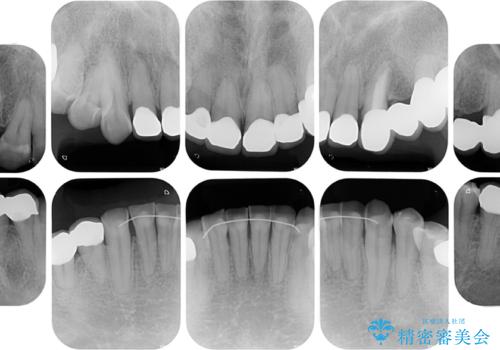

矯正治療は想定通り長期化しましたが、しっかりと奥歯の咬み合わせを向上させて前歯の被蓋を改善させることができました。

目立つ銀歯やすり減った前歯がセラミッククラウンとなり、患者様には大変満足していただけました。